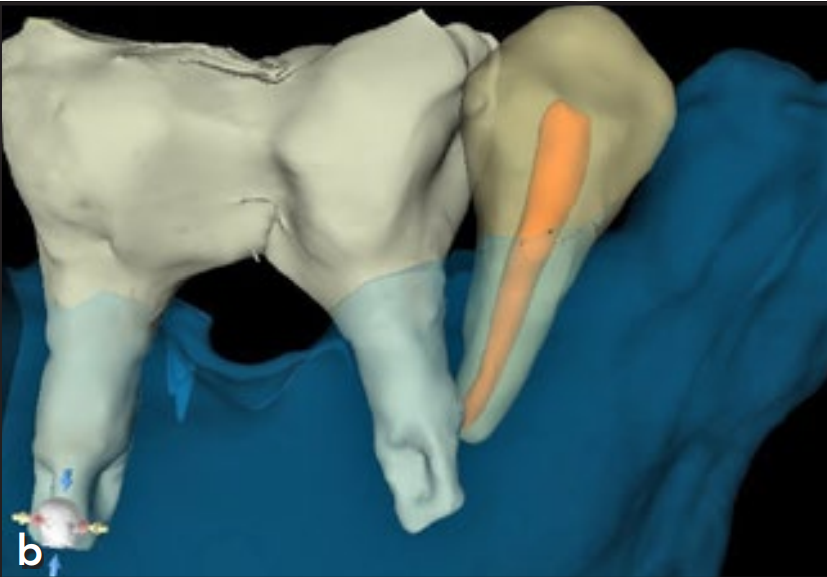

1周后临床检查显示#44牙髓活力测试(冷测)无反应,确诊牙髓坏死。患者转诊至牙体牙髓科行根管治疗,2周后X线检查发现根尖区透射影。术后2个月,#46位点种植体出现松动伴脓性渗出,诊断为早期失败,予以取出并行手动清创(配合0.12%氯己定冲洗)。同期对#45位点种植体完成二期手术(图2a)。

3个月后,于原失败位点(#46)植入新MK III Brånemark种植体(常规平台,10mm),同期影像显示种植体就位良好(图2b)。

注意下颌右侧第一前磨牙的根尖神经横断。(a) 横断面图像。(b) 3D立体图。